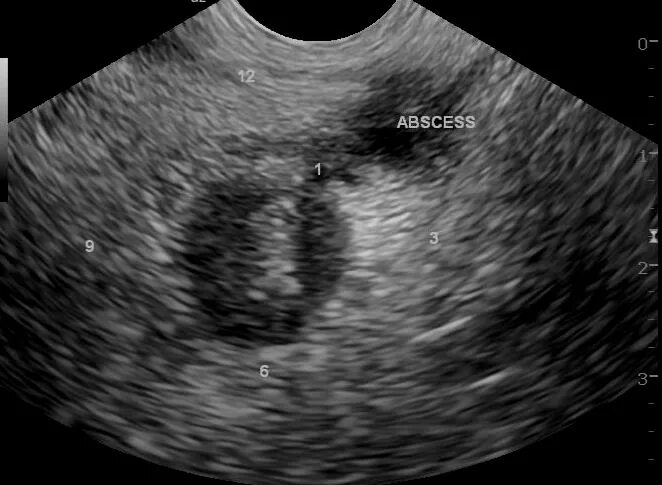

Абсцесс при аппендиците